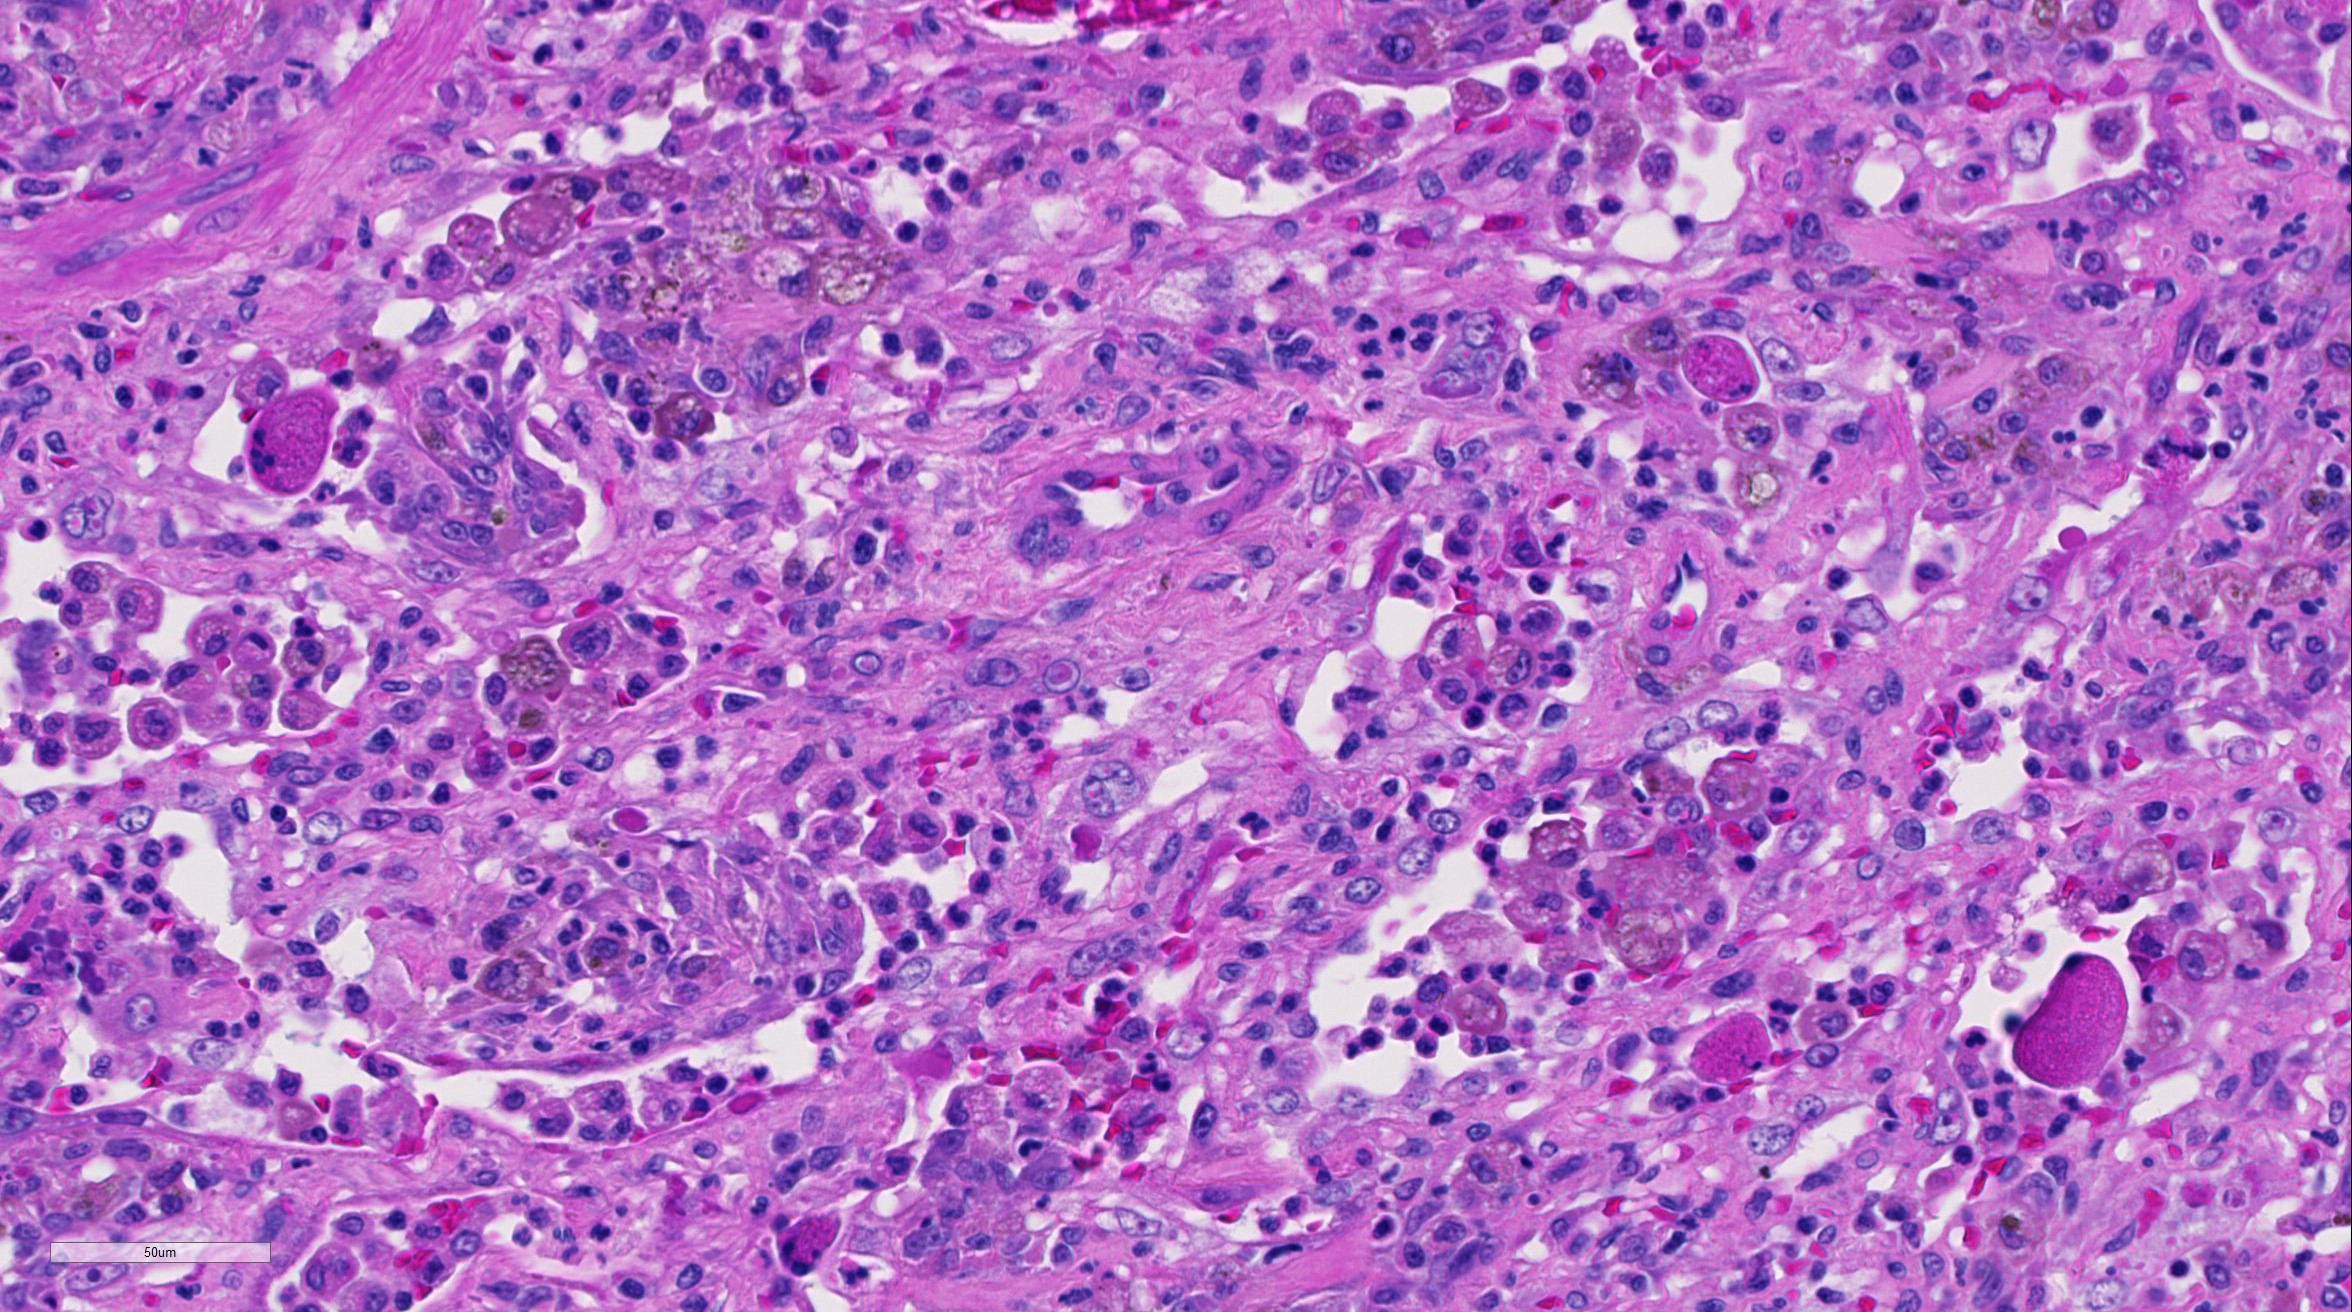

| 40X   |   Hematoxylin and Eosin | ||||

Lung: There is alveolar type II pneumocyte hyperplasia and pneumocytes are often multinucleated with up to eight nuclei (viral syncytia) and frequently contain 4um eosinophilic intracytoplasmic and intranuclear inclusion bodies; these syncytial cells are often hypereosinophilic with karryorhectic nuclei (necrosis) and have been sloughed into alveolar lumina.